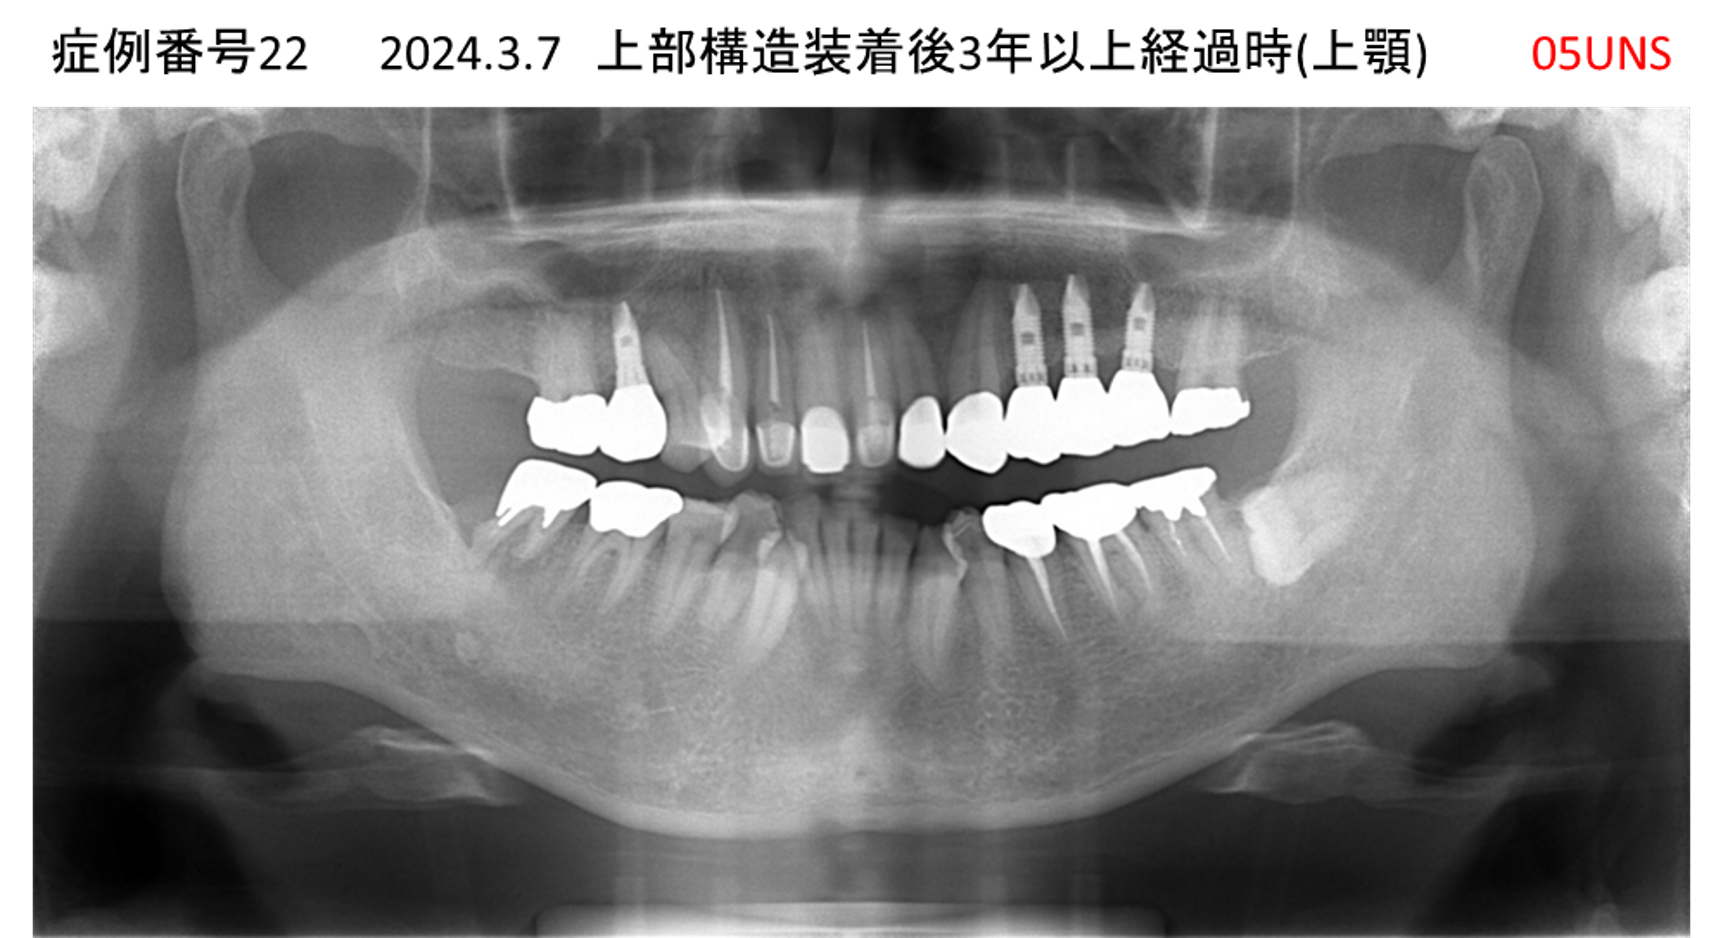

全く噛めない患者様のインプラント症例

| 治療名称 |

インプラントAGC |

| 治療費用 |

860万円+税 |

| 治療期間 |

12か月 |

| 患者さんの症状(主訴) |

全く噛めない、ごはんが後もに食べられるようになりたい、人前で口元を隠したくない |

| 治療内容 |

サイナスリフト、GBR、インプラント、AGC |

| 治療結果 |

しっかり噛めて踏ん張ることができる。食べ物をを選ばなくて済む、何でも食べられる、体重が増えた。見栄えがきれいすぎて自分じゃないみたい |

| 治療の注意点(リスク/副作用) |

インプラントが壊れたら再治療が必要 |